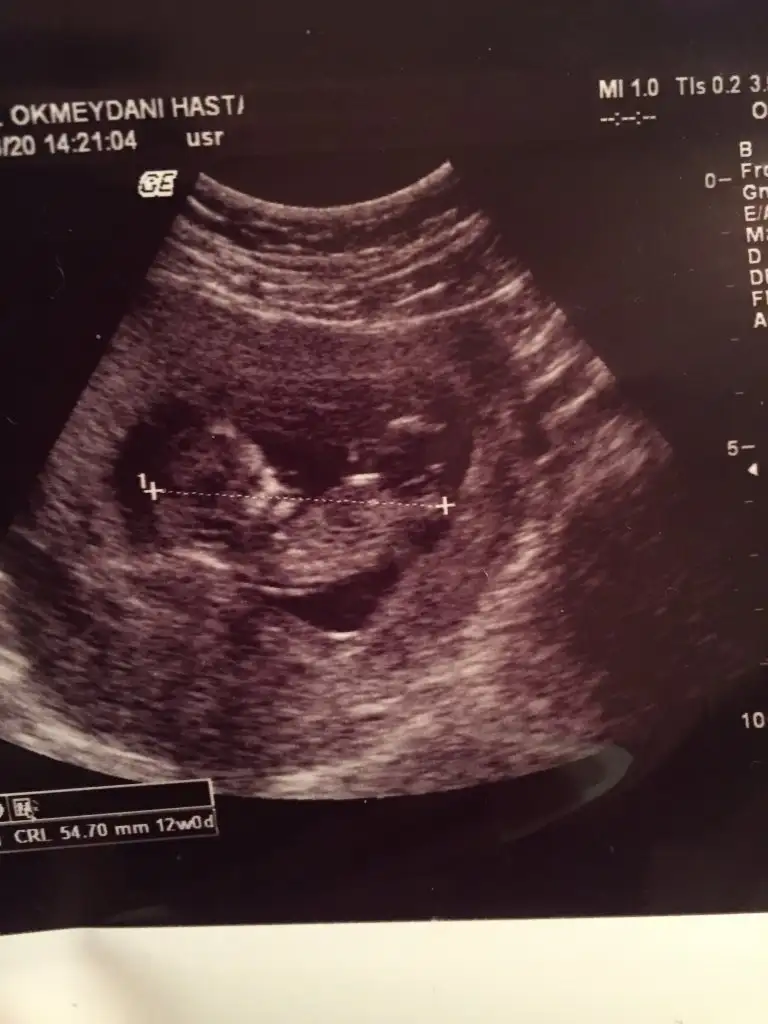

10+5 iz bizede bi tahminde bulunabilirmisiniz çok merak ediyorum cinsiyetini

• IMG_20200402_110756.webp

IMG_20200402_110756.webp

17,7 KB · Görüntüleme: 45

• IMG_20200402_110735.webp

IMG_20200402_110735.webp

12,3 KB · Görüntüleme: 42

• IMG_20200402_110732.webp

IMG_20200402_110732.webp

11,1 KB · Görüntüleme: 52